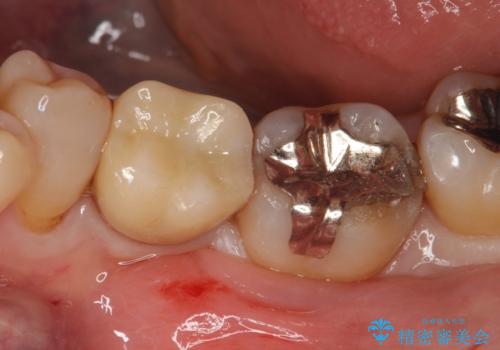

メタルインレーの下は。クラックラインを認めた歯。

- 定期検診にて、奥歯にクラックラインを認めました。

放置すると、抜歯になる可能性も高いため早めの治療を提案し、クラウンにて修復治療を行なっております。

術前説明にてクラックラインを認めることや治療の選択肢及び予後について理解していただいた上で、保存を希望されております。歯髄症状が出なかったため抜髄はせずに治療を完了しております。